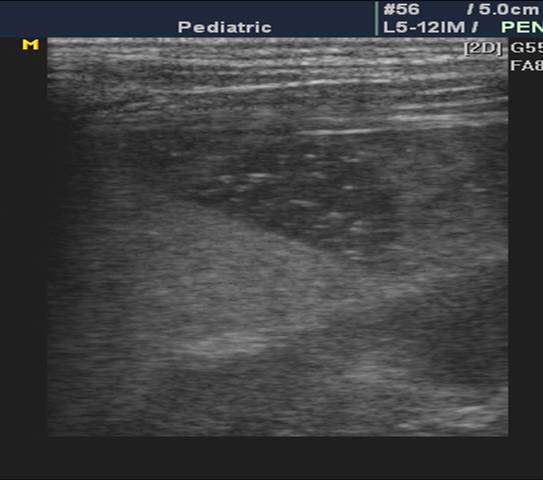

假性脾囊肿: